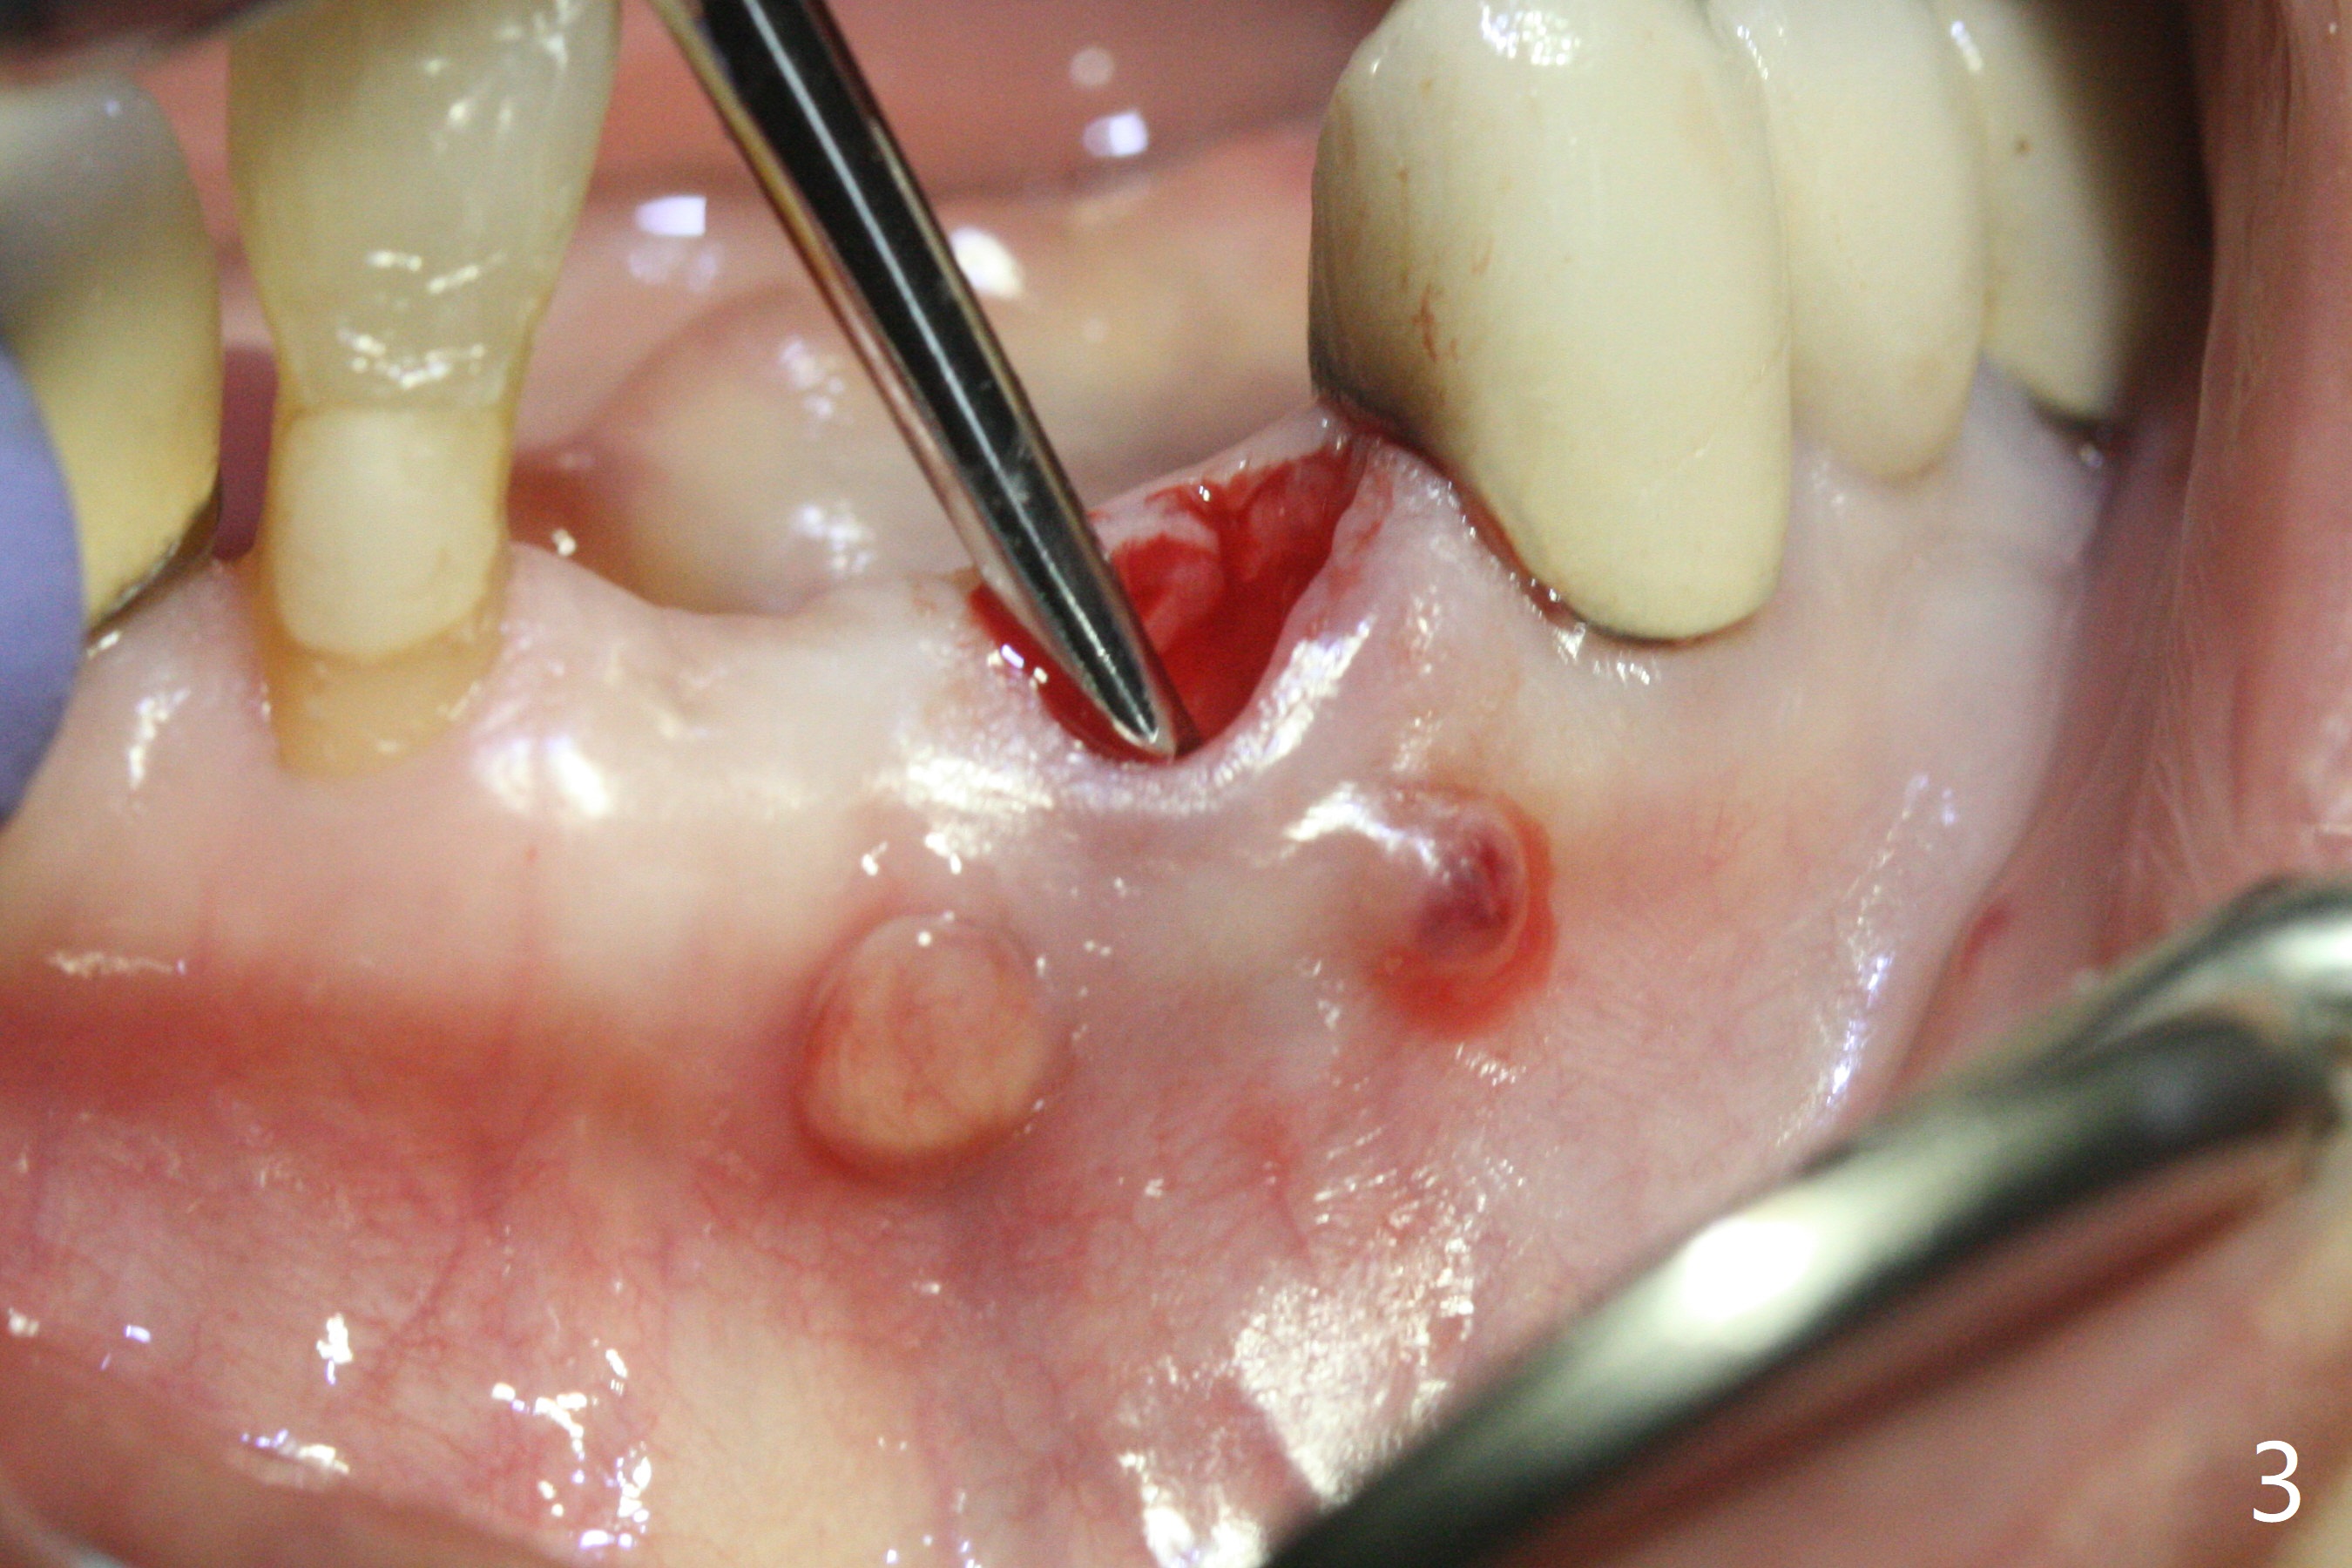

A 64-year-old woman requests extraction of the tooth #23 for lower partial (Fig.1). Since there are 2 buccal sinus tracks, another residual root is suspected (?). After shown loss of the buccal plate (Fig.2,3), the patient agrees to have socket preservation with allograft (Fig.5,6 *) and BioXclude (Fig.4 >). The suspected residual root is not explored considering the 2 sinus tracks being associated with the lesion of #23 (Fig.2,3). Cytoplast is not used because of time constraint and fear of gingival dehiscence associated with extensive dissection. In fact the sinus tracks shrink in a week, while the buccal plate remains bulging (Fig.7 *) and the socket heals (Fig.8 >). The buccal plate is flat (no swelling) 1 month postop (Fig.9).